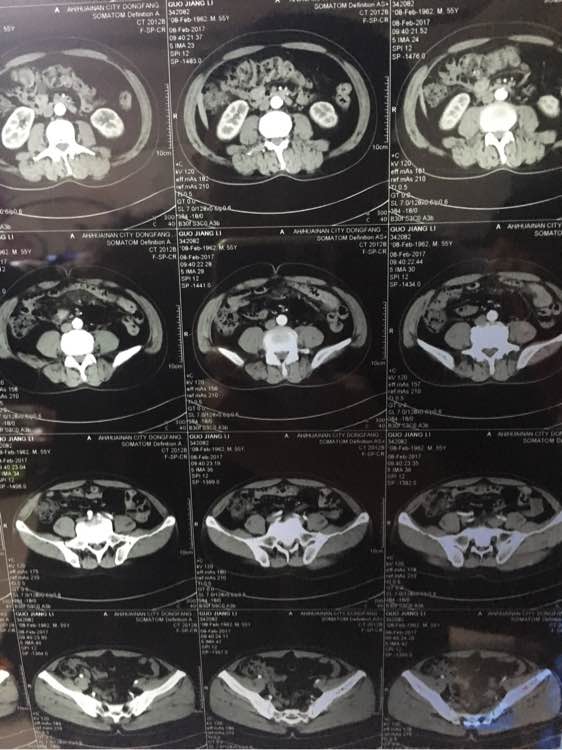

大神看下,几个月前说肠子

几个月前说有点东西,肠子上

兄弟 你拍的有点多啊 全腹部ct?